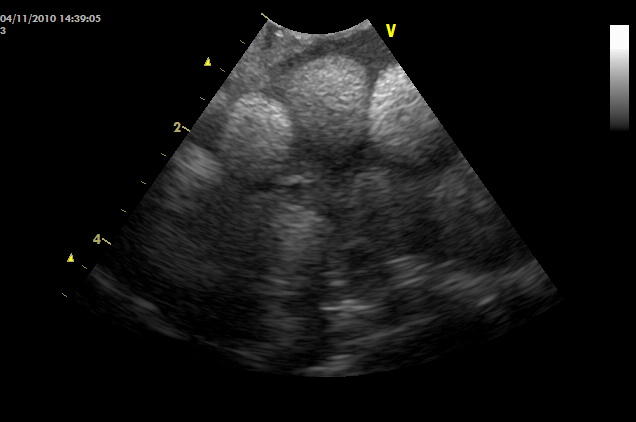

メスが繁殖期を迎えて卵ができたら、一般的に無精卵を産むか、卵が吸収してなくなるかのどちらかです。メスを飼育されている人が、「うちのグリーンイグアナは発情期になっても卵を産まない」という声も聞きますが、よく調べると卵ができて自然に吸収してなくなっていることもありえます。卵ができると2~3カ月の時間を要して無精卵が産み出されます。卵が大きくなるにつれて、拒食、腹部膨満、地面を掘るなどの症状がみられるようになります。卵ができると最初に卵殻がない黄色の卵胞(らんぽう)が形成されます。一つの卵巣に何十個もの卵胞ができるので、まるでブドウの房のようです。卵胞はX線にはうつらないので、超音波検査で診断します。

卵胞を超音波でみると、多数の球状の影としてうつしだされます。

イグアナが産卵する環境でないと判断した場合、卵胞ならば自然に吸収して、縮小しまうこともあります。